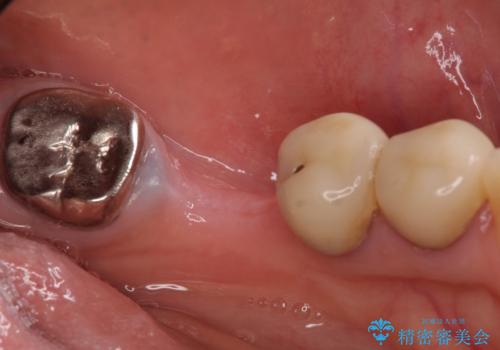

骨を増やすための手術が必要になるので、通常のインプラント治療より手術回数が一回多くなってしまうのがデメリットですが、将来的に安定したインプラントにするため、骨造成手術を前もって行いました。

しっかりとした骨幅を獲得し、理想的な太さのインプラントを埋入することができました。